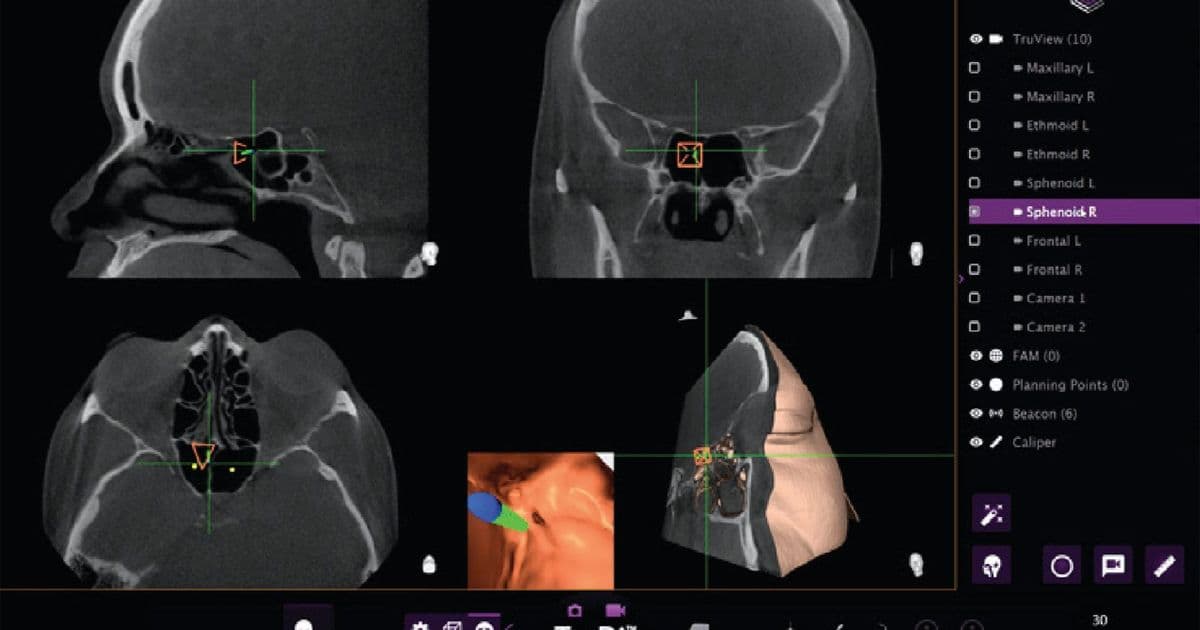

The TruDi system, designed to simplify surgical planning and provide real-time feedback during delicate sinus procedures, experienced a dramatic increase in reported malfunctions after AI algorithms were integrated. Before the AI enhancement, the device had documented eight malfunctions over three years on the market. Following the AI integration, that number jumped to at least 100 malfunctions and adverse events, according to the Reuters report.